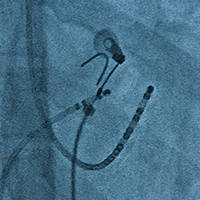

今年新設の不整脈コース。アブレーション/植え込みデバイスビデオライブ、レクチャーセッションと、コメディカルコースでは入門編をお届けいたします。